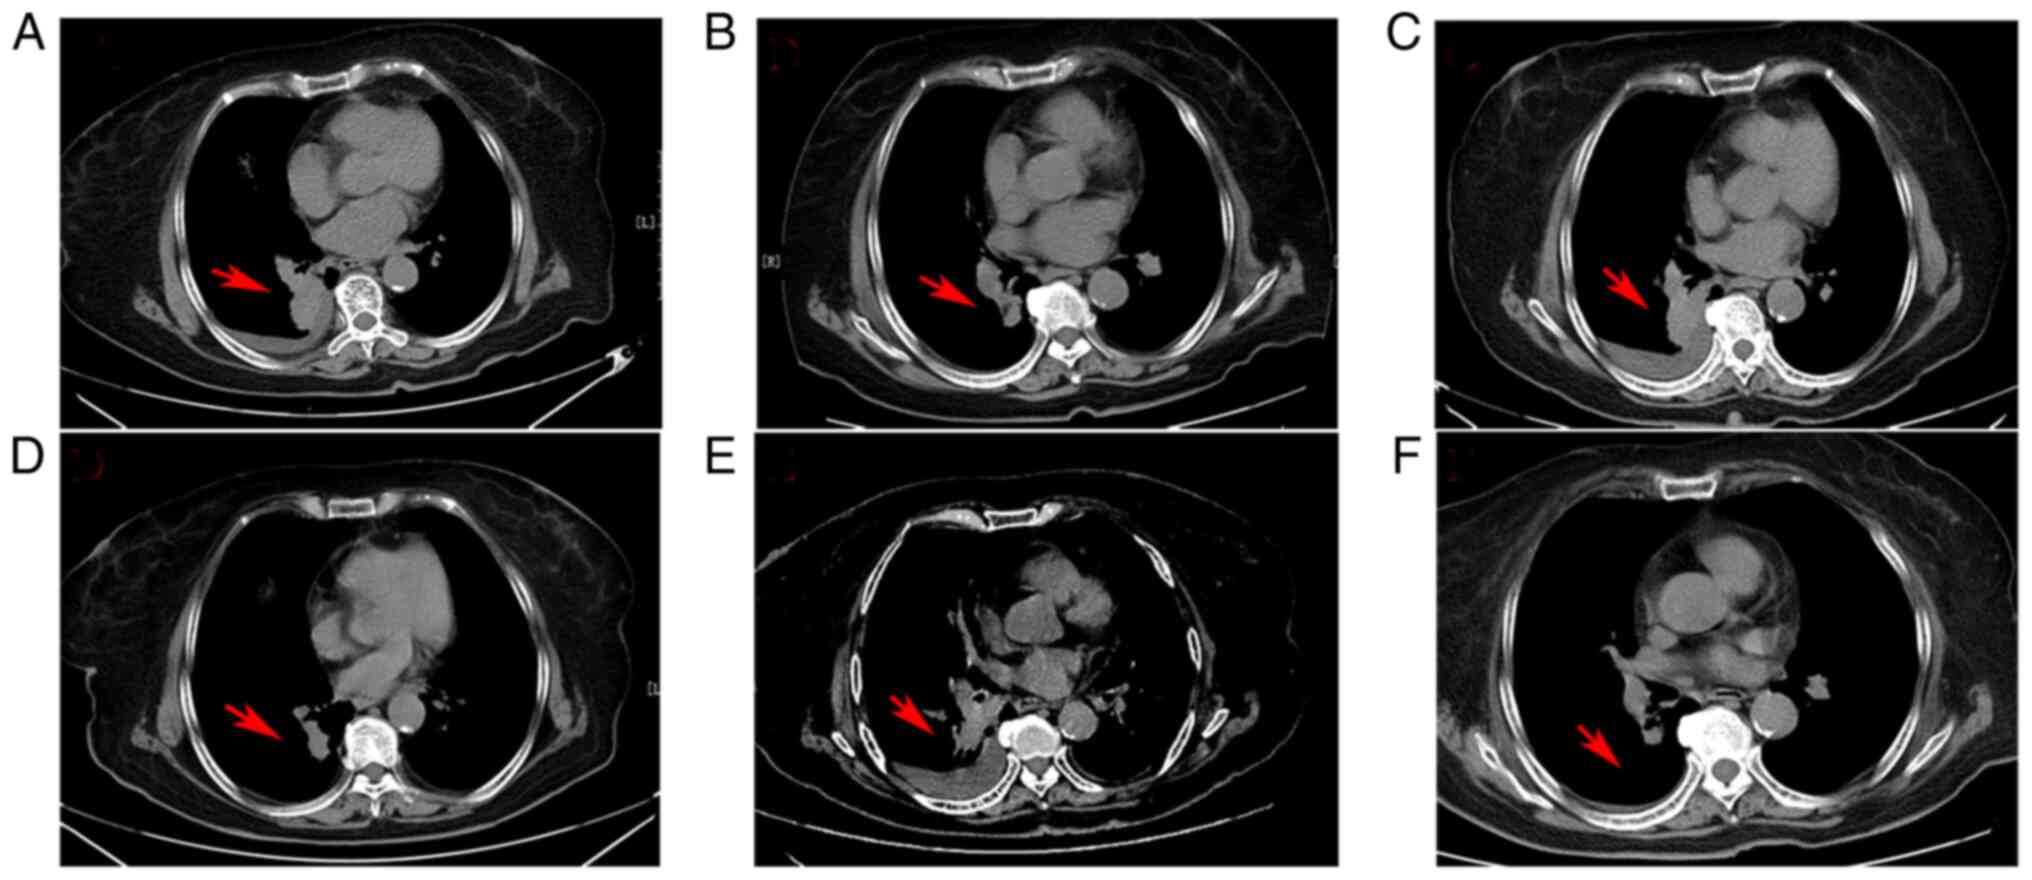

Figure 1.

Radiological images showing the changes in patient 1 during the total treatment period. (A) The initial computed tomography scan showed a tumor (3.6×3.1 cm) in the inferior lobe of the right lung at diagnosis (January 2021). (B) The tumor decreased to 2.8×1.8 cm after osimertinib treatment for 2 months (April 2021). (C). The tumor increased to 3.7×3.2 cm after osimertinib for 5 months (July 2021). (D) The tumor shrunk to 1.5×1.2 cm after aumolertinib for 2 months (September 2021). (E) The tumor enlarged to 3.7×3.2 cm after aumolertinib interruption for 2 weeks due to mild acute pancreatitis (September 2021). (F) The lesion disappeared after resuming aumolertinib treatment for 6 weeks (November 2021). The tumor location is indicated by the red arrow.

The CSCO NSCLC guidelines (2021 version) have recommended both osimertinib and aumolertinib as first-line treatments for patients with stage IV NSCLC harboring EGFR–sensitive mutations (12). However, aumolertinib is not included under Chinese basic medical insurance, whereas osimertinib is. At 2 weeks post-admission, the patient was started on osimertinib at the standard dose of 80 mg once daily. After 2 months, the first efficacy evaluation revealed that the lung lesion had decreased in size markedly, and the pleural effusion had disappeared, indicating that partial remission (PR) had been achieved (Fig. 1B). Thereafter, efficacy was regularly assessed every 1–2 months. After 5 months of osimertinib treatment, however, a chest CT scan revealed that the primary lung foci appeared significantly larger, and the pleural effusion had increased in size again (Fig. 1C). The clinical efficacy result was assessed as progressive disease (PD), suggesting the existence of osimertinib resistance. Furthermore, EGFR gene mutant status was examined in a peripheral blood sample, revealing an EGFR exon 20-T790M mutation. Due to the frailty and advanced age of the patient, chemotherapy plus antiangiogenic therapy was refused.

After sufficient communication, the patient was treated with oral aumolertinib (110 mg per day) beginning in July 2021. Unexpectedly, a substantial PR response was achieved again after 2 months (Fig. 1D). However, at this time, the patient experienced mild acute pancreatitis, and aumolertinib therapy was paused. The patient recovered completely from the acute pancreatitis within 2 weeks. In September 2021, the patient complained of mild chest tightness and chest discomfort. Chest CT imaging revealed that the primary lung foci and pleural effusion had progressed again (Fig. 1E), and aumolertinib therapy was re-instated. The patient achieved PR once again (Fig. 1F). To date, the patient is continuing on aumolertinib treatment and stable disease has been recorded. The first and second PR periods for aumolertinib were 2.0 and 8 months, respectively. The total PFS time (defined as the time from the initial treatment of aumolertinib to disease progression) was 10 months (at the time of writing this study).